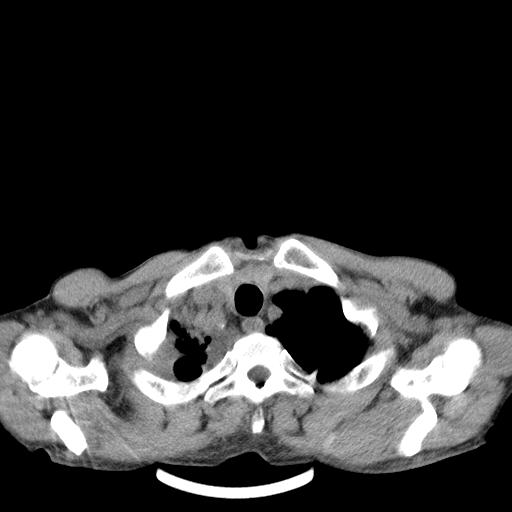

男性 75  咳嗽 一周前发热最高达39

右肺继发型tb并右侧tb性胸腔炎,右侧胸腔大量积液并右下肺膨胀不全,慢支肺气肿、多发肺大泡。建议抽胸水实验室检查并复查排除恶性在占位。

右上肺继发型肺结核,右胸腔中等量积液。

左上肺大泡。

1)右肺继发型肺结核。2)左肺胸膜下多发性肺大泡。3)右侧胸腔积液。